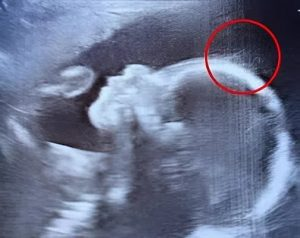

While performing the ultrasound, the sonographer looked at the monitor all puzzled, but then she smiled and said, “Wait a minute. Is that hair?” One of the doctors approached closer and said jokingly, “Looks like you’ve got a little rock star in there — she might just skip the baby baldness entirely!”

Indeed, the ultrasound showed wispy strands swaying underwater like seaweed.